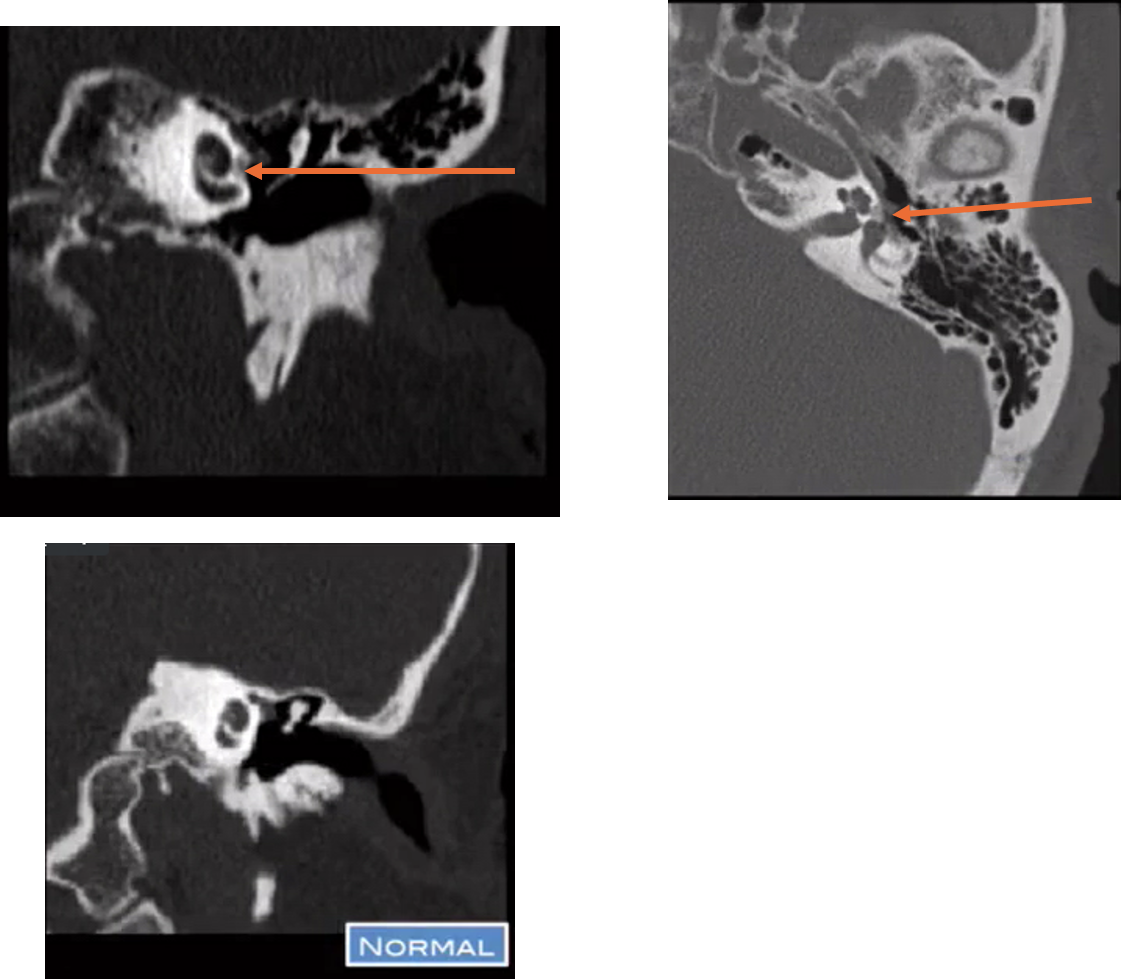

otosclerosis (otospongiosis)

demineralization at the fissula ante fenestram

in otosclerosis where does demineralization typically occur?

fissula ante fenestram